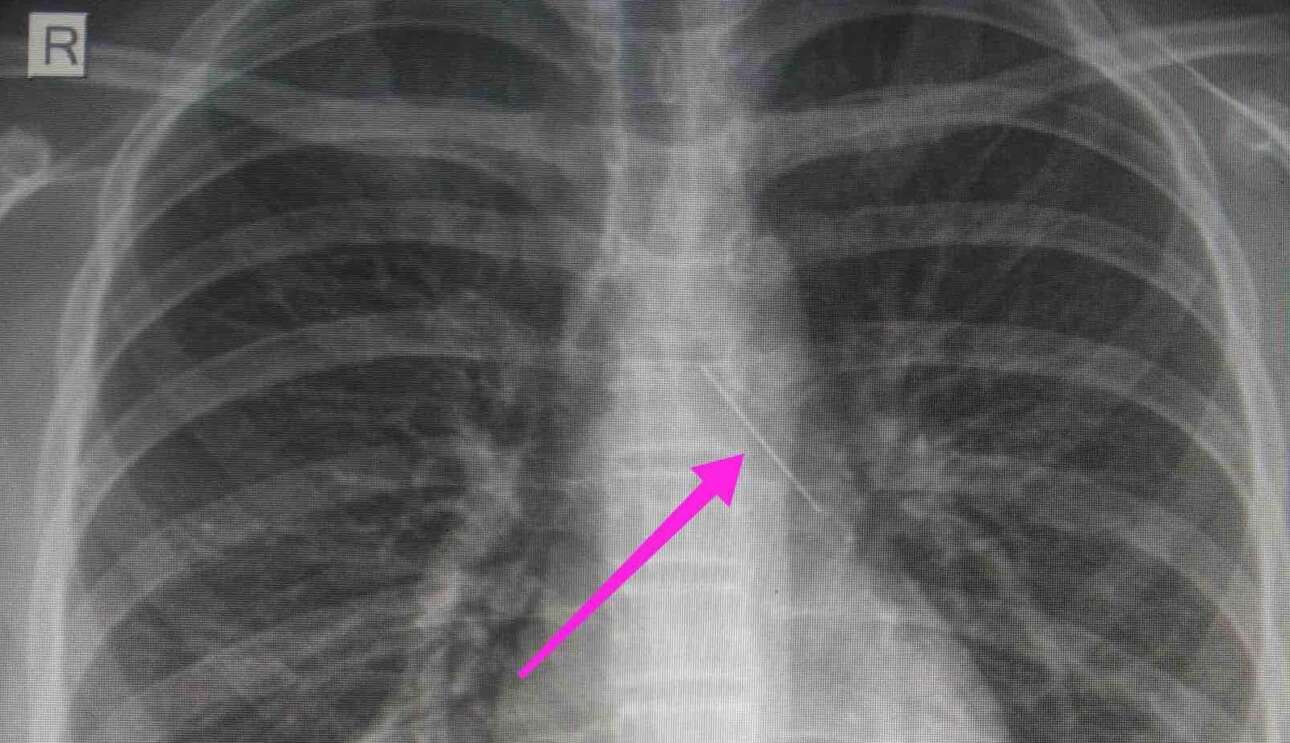

Σύμφωνα με ανάρτηση του νοσοκομείου στο Facebook, «από την αρχική απεικονιστική διερεύνηση που πραγματοποιήθηκε με ακτινογραφία θώρακος και ακολούθως με αξονική τομογραφία θώρακος, διαπιστώθηκε η ύπαρξη αιχμηρού μεταλλικού ξένου σώματος στην αναπνευστική οδό (αριστερός κύριος βρόγχος) και όχι στην πεπτική οδό».

Η ανήλικη υπεβλήθη σε βρογχοσκόπηση και διαπιστώθηκε η μετακίνηση και ενσφήνωση του ξένου σώματος στον δεξιό κύριο βρόγχο. Επειτα από εργώδεις προσπάθειες, ολοκληρώθηκε με επιτυχία η αφαίρεση της καρφίτσας.